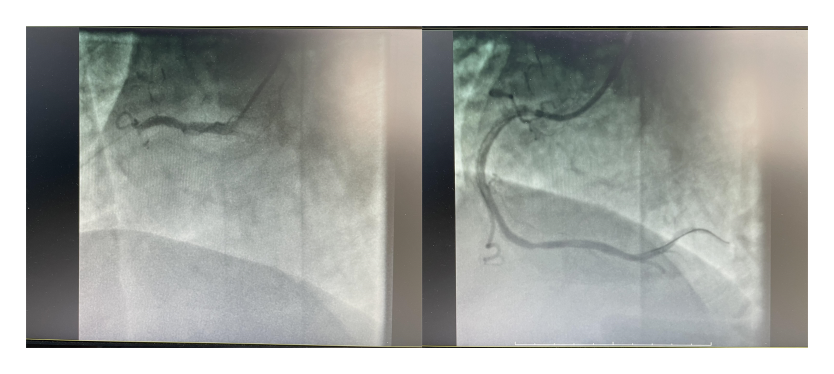

晚上19點(diǎn)25分,患者到達(dá)介入醫(yī)學(xué)科,老年醫(yī)學(xué)科/心血管內(nèi)科二病區(qū)康主任帶領(lǐng)團(tuán)隊(duì)用時(shí)30分鐘左右,迅速為患者完成急診介入手術(shù),術(shù)中情況和初診判斷一致,右冠狀動(dòng)脈近段閉塞100%。抽出大量大塊血栓并植入支架后,患者右側(cè)冠狀動(dòng)脈恢復(fù)血流,安返病房。

介入治療前后右冠狀動(dòng)脈造影圖像